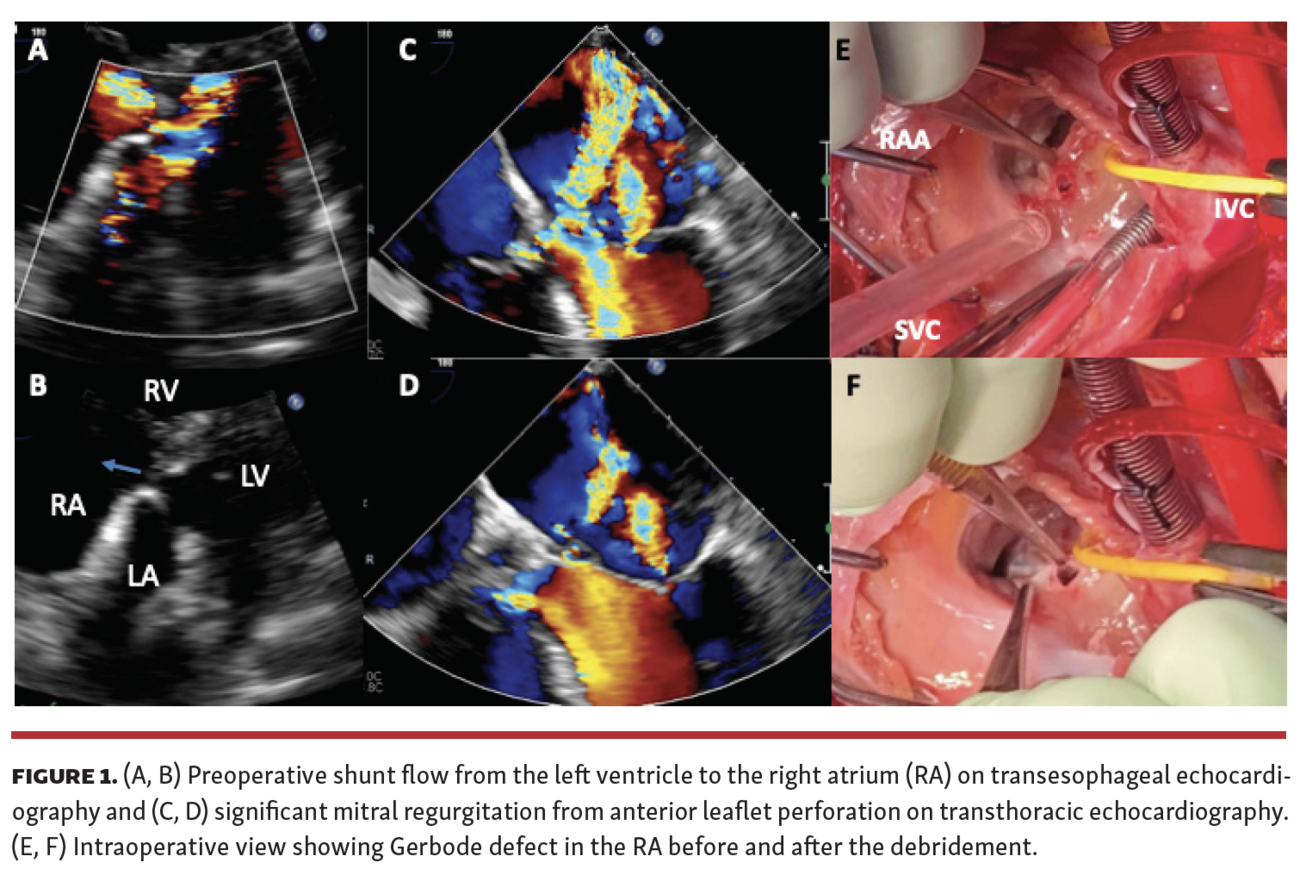

A 52-year-old woman with no known cardiac history developed infective endocarditis of the mitral and tricuspid valves caused by methicillin-sensitive Staphylococcus aureus following skin infection. She demonstrated complete heart block and severe mitral regurgitation (perforation in the anterior leaflet), moderate tricuspid regurgitation with vegetation at the base of the septal leaflet, and a shunt (left-right) from the left ventricle to the right atrium (Figure 1 and Video Series). At surgery, we debrided the mitral and tricuspid valves, and replaced them with tissue prosthetic valves. The inlet of the defect was confirmed to be immediately behind the A2 mitral leaflet. In the right atrium, we identified the shunting defect just in front of the anterior-septum commissure connecting to perimembranous septum (Figure 1). Infective tissue was also observed surrounding the outlet of the defect and was debrided. The defect was closed with autologous pericardium. Postoperative echocardiographic findings were satisfactory without residual shunt flow or perivalvular leak (Video Series). Postoperative recovery was uneventful without infection recurrence. Gerbode defect is a rare complication of infective endocarditis and careful preoperative echocardiographic work-up is imperative for successful repair.